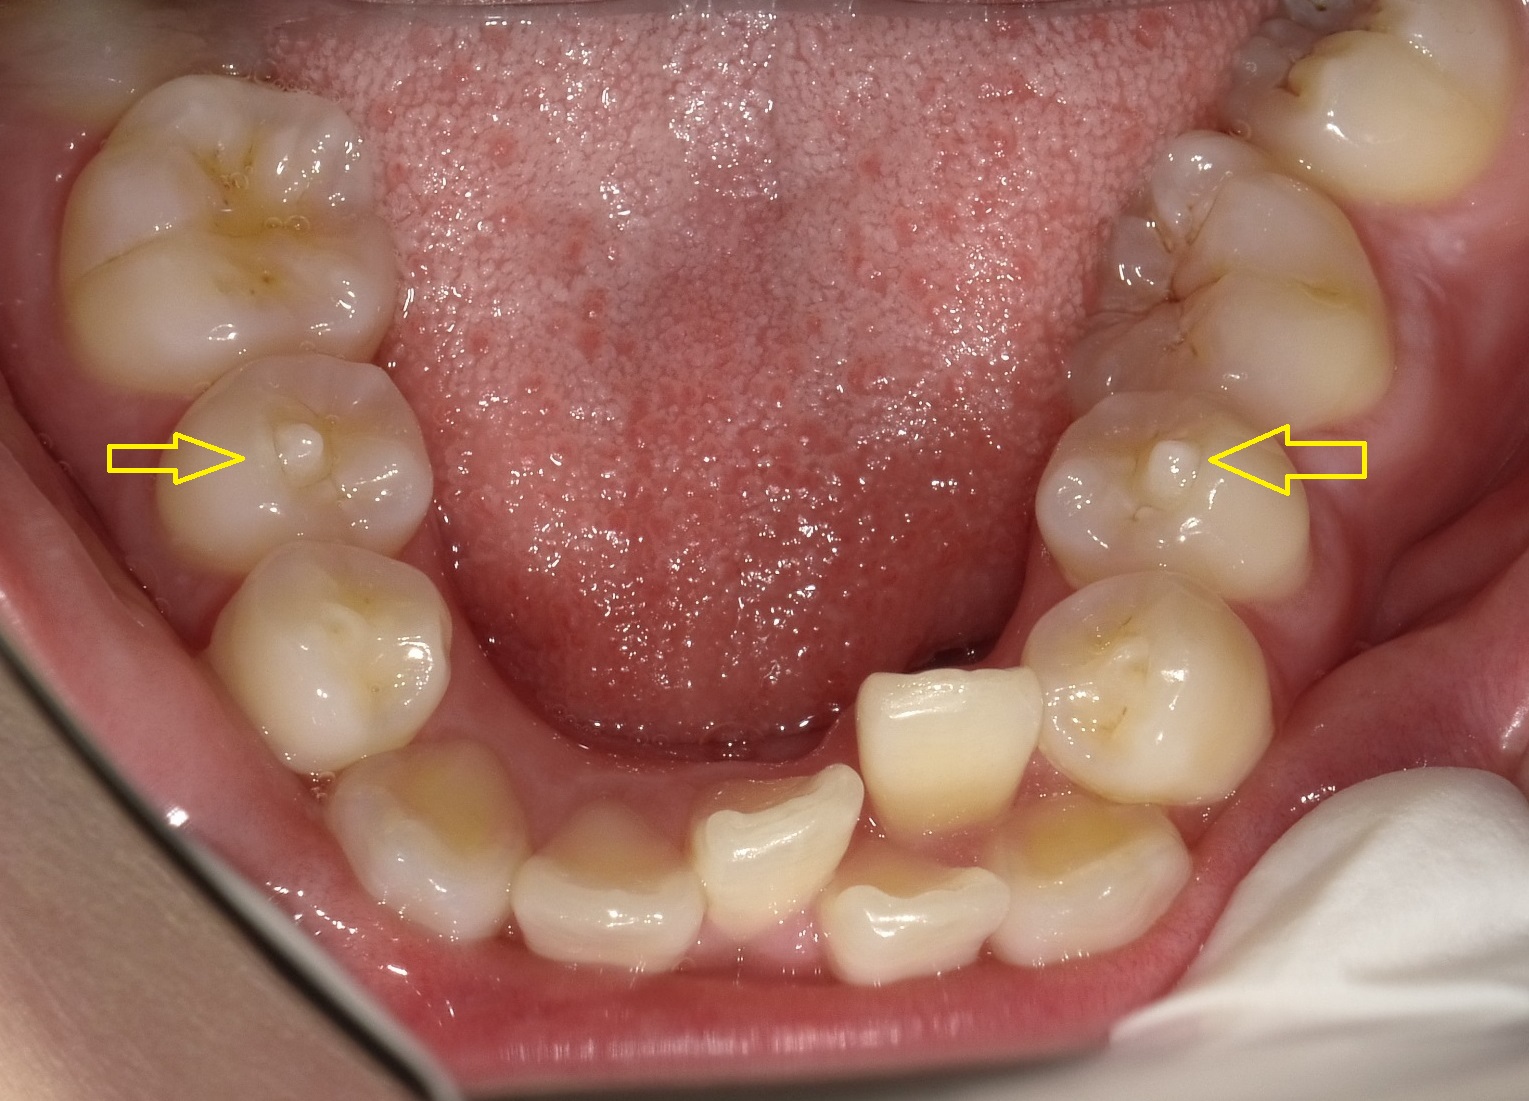

また、留意点として奥から3番目の矢印の歯の噛む面に突起があります。

これは中に神経の管が通っていることがあり、不必要に削ったり折れたりすると、神経症状が出てしまうことがあるため矯正治療で噛み合わせを作る際に過度に負担が掛からないようにする必要があります。